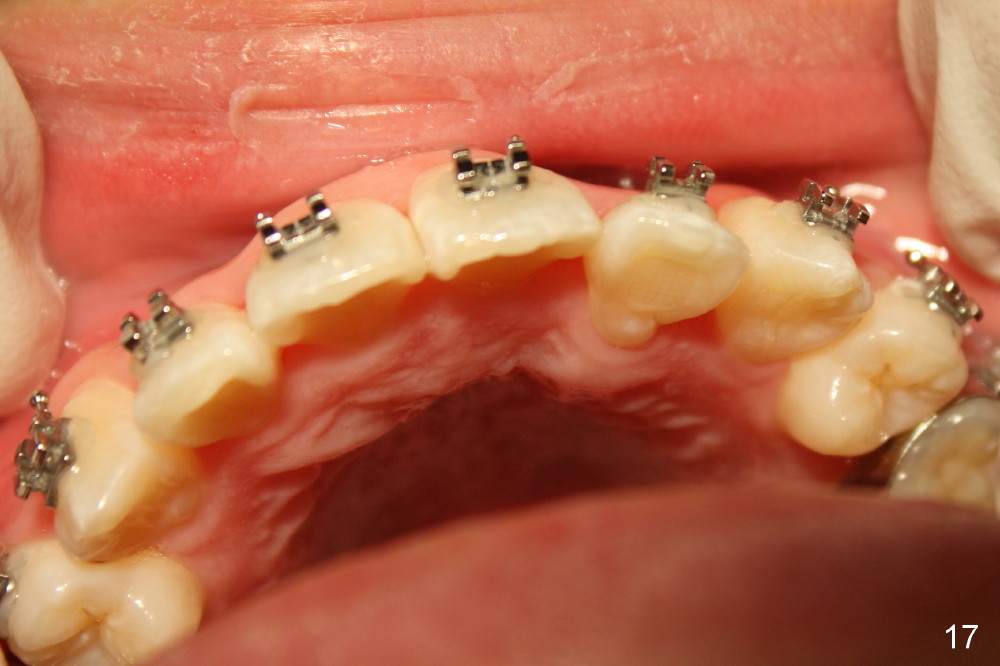

Seven months of treatment, the dental midlines coincide (Fig.13 dashed lines). Extraction spaces have been closed or being closed (Fig.13-15). UL 2 has been moved into the arch (Fig.13,15,16). But the alignment needs to be improved with arch wire sequence for a second time starting with .0175 twisted wire (Fig.13-16).

The alignment of UL2 improves one month of using .016x.022 ss wire with introduction of torque (total 14 months of treatment, Fig.17). The open bite (Fig.1-4, ignored), basically corrected nearly in the end of treatment (Fig.13-15), relapses < 2 years.